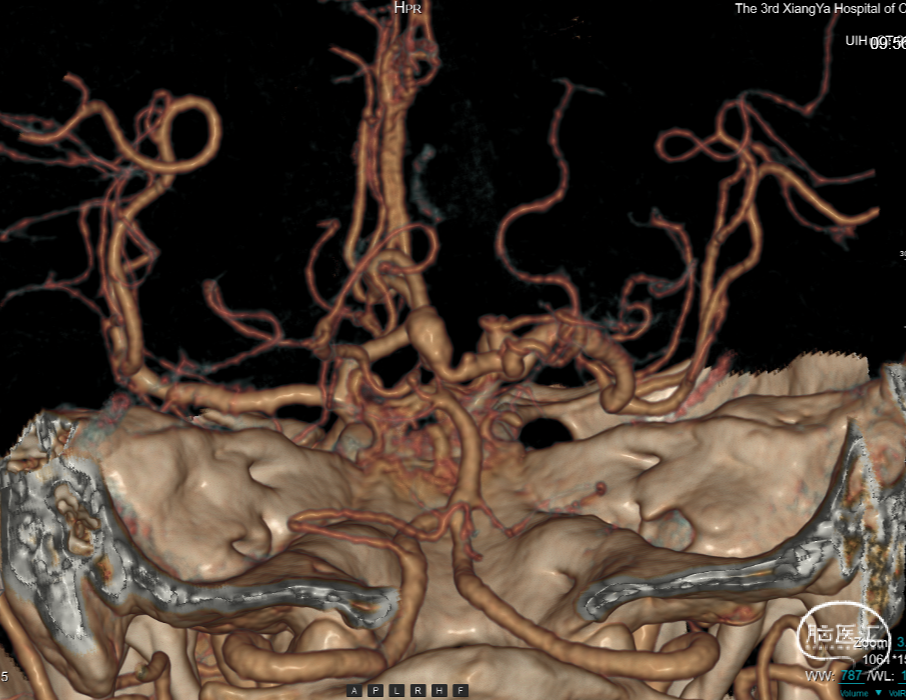

外院CTA示:

1.右侧大脑脚-右侧丘脑急性脑梗死。

2.右侧大脑后动脉P1、2段显影差,P3及其以下未见显影;建议结合临床。

3.结合CTA,符合右侧颈内动脉C7、基底动脉末端动脉瘤。

4.鼻窦炎。

右侧中脑-丘脑可见新发脑梗塞:

颅内外血管未见明显狭窄。

CT(CTA)检查提示:右颈内动脉C7段大小约3.6×3.8×3.6mm及基底动脉远端动脉瘤形成大小约9.7×7.6×9.3mm。

DSA:右侧P1段一6.8*9.7mm不规则囊状突起动脉瘤,远端P2段呈螺旋状蛇形动脉瘤改变。

DSA:右侧P1段一6.8*9.7mm不规则囊状突起动脉瘤,右侧A1段动脉瘤。夹层蛇形动脉瘤。

DSA:评估右侧后交通。

右侧颈内正位

右侧颈内3D

椎动脉压颈3D